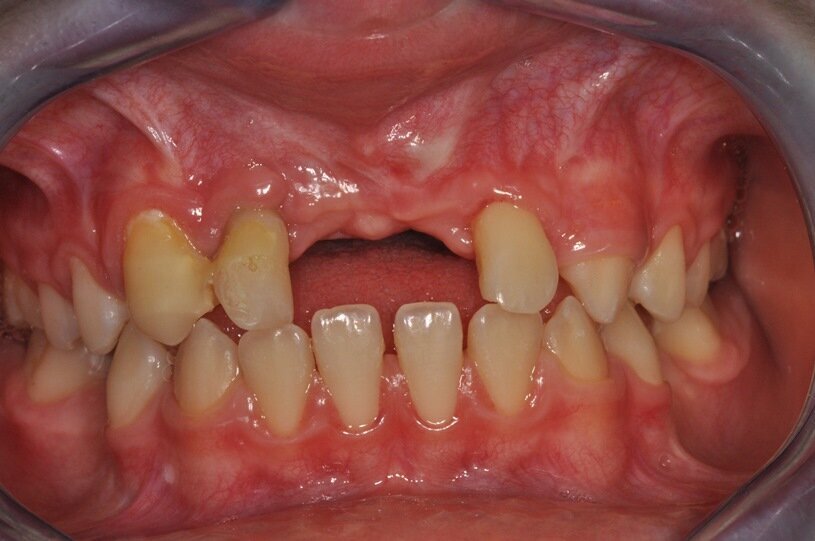

W dniu wizyty w poradni brak było oznak ostrego stanu zapalnego w okolicy 12-11. Widoczne były recesje dziąsła o wysokości 2 mm po stronie wargowej na zębach siecznych górnych przyśrodkowych, zmniejszona wysokość dziąsła zrogowaciałego do wartości 2 mm, spłycony przedsionek (Ryc. 1). Zęby były tkliwe na opukiwanie pionowe i poziome oraz wykazywały I stopień rozchwiania wg Entina. W przekrojach TK widoczny był rozległy przewlekły stan zapalny wokół wierzchołków korzeni zębów 11 i 21 (Ryc. 2), brak blaszki przedsionkowej wyrostka zębodołowego szczęki oraz resorpcja korzeni. Po wnikliwej analizie stanu miejscowego i rozmowie z rodzicami zadecydowano o ekstrakcji zębów 11 i 21 oraz w drugim etapie, ze względu na rozległy i zaawansowany proces zapalny, o autotransplantacji zawiązków 35 i 45.

Ryc. 1_Stan miejscowy przed ekstrakcja zębów 11 i 21.